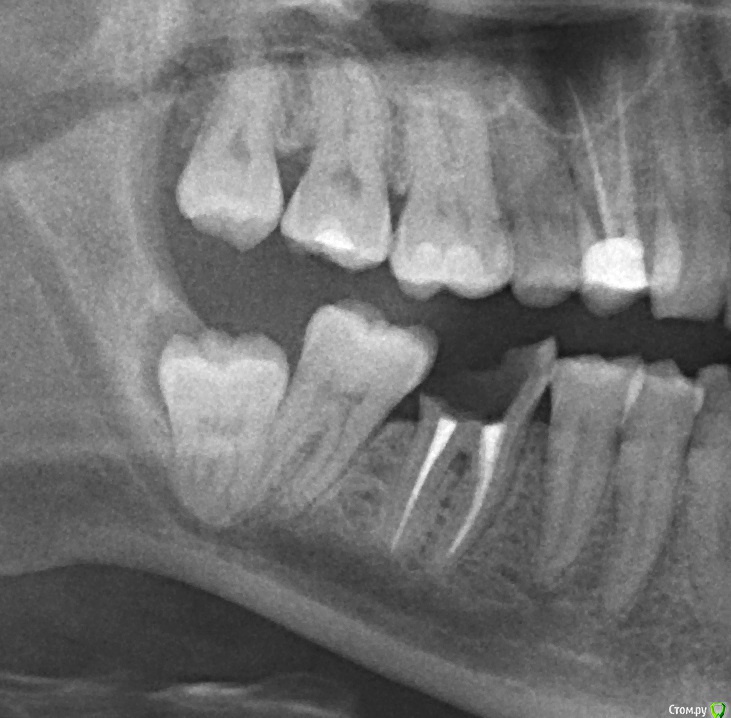

hysteresis Опубликовано 17 февраля, 2015 Поделиться Опубликовано 17 февраля, 2015 (изменено) Около года назад оживился зуб мудрости. Появились следующие проблемы:1. Периодически (раз в 3-4 месяца) боль в скуле2. Соседний 7-ой зуб по ощущениям стал выше - челюсть нормально не смыкается (но на снимках этого не замечаю).3. Легкое оглушение в ухе со стороны зуба, почти постоянно. Изредка боль в ухе. Это снимок 2012-го года. Это снимок 2015-го года. Нужно ли удалять? Или точнее можно ли не удалять, хирург предупредил о возможном осложнении в виде повреждения нерва. Я этого опасаюсь. Могут ли быть связаны проблемы с ухом с этим зубом?Исправит ли удаление 8-ки "изменение высоты" 7-ки. Или как это вообще исправить? Два разных стоматолога рекомендовали удалять в стационаре. Теперь хирург берется удалить всё на месте. Этот тоже добавляет некоторые сомнения. мой возраст 36 лет. Изменено 17 февраля, 2015 пользователем hysteresis Ссылка на комментарий

Bier Опубликовано 17 февраля, 2015 Поделиться Опубликовано 17 февраля, 2015 зуб Ваш подрос и больше не касается нерва. Все легко удаляется в кресле. И верхний и нижний. 2 Ссылка на комментарий